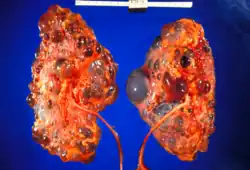

Renal pathology

Renal pathology is a subspecialty of anatomic pathology that deals with the diagnosis and characterization of disease of the kidneys. In a medical setting, renal pathologists work closely with nephrologists and transplant surgeons, who typically obtain diagnostic specimens via percutaneous renal biopsy. The renal pathologist must synthesize findings from traditional microscope histology, electron microscopy, and immunofluorescence to obtain a definitive diagnosis. Medical renal diseases may affect the glomerulus, the tubules and interstitium, the vessels, or a combination of these compartments.